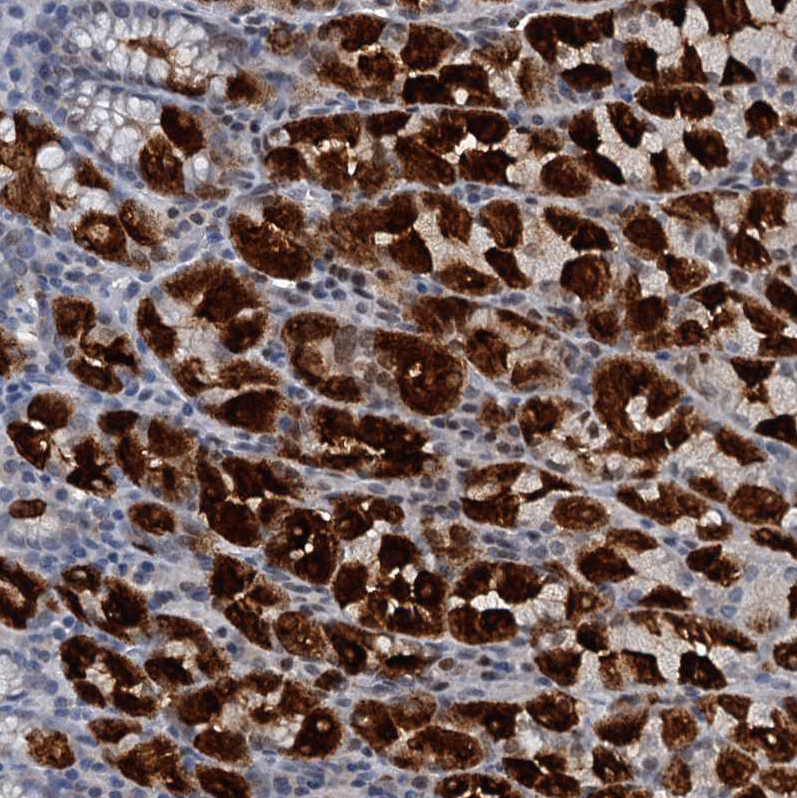

Immunohistochemistry analysis in human stomach and skeletal muscle tissues using HPA039908 antibody. Corresponding GIF RNA-seq data are presented for the same tissues.